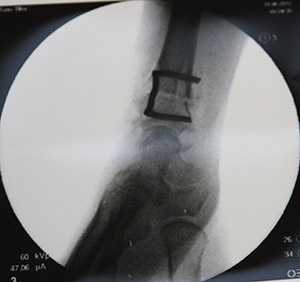

Снимок после укорочения лучевой кости

Элегантный способ фиксации остеотомии скобкой.

Вернемся к нашей героине, которая столкнулась с проблемой запястья накануне свадьбы. За месяц до намеченной даты была выполнена операция — остеотомия лучевой кости.